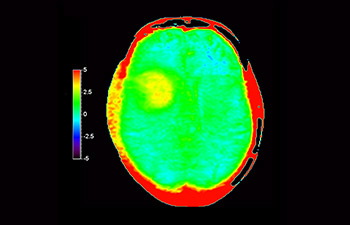

Dans une société où les troubles neurologiques sont importants, Philips s’engage à fournir une qualité de diagnostic irréprochable et la meilleure orientation thérapeutique pour tous les patients. De nos jours, même si l’IRM est une référence en imagerie neuro-oncologique, sa précision en termes de classement des tumeurs et l’évaluation du suivi du traitement peuvent être davantage améliorées. 3D APT (Transfert de proton amide) est une nouvelle méthode d’IRM cérébrale unique et sans contraste qui répond au besoin de fiabilité pour les diagnostics neuro-oncologiques. 3D APT utilise la présence de protéines cellulaires endogènes pour produire un signal RM qui est directement lié à la prolifération cellulaire, indicateur de l’activité tumorale. 3D APT peut aider les professionnels de santé formés à différencier les gliomes cérébraux de haut grade par rapport aux gliomes cérébraux de bas grade, ainsi que l’évolution de la tumeur par rapport aux effets du traitement1.

avec 3D APT